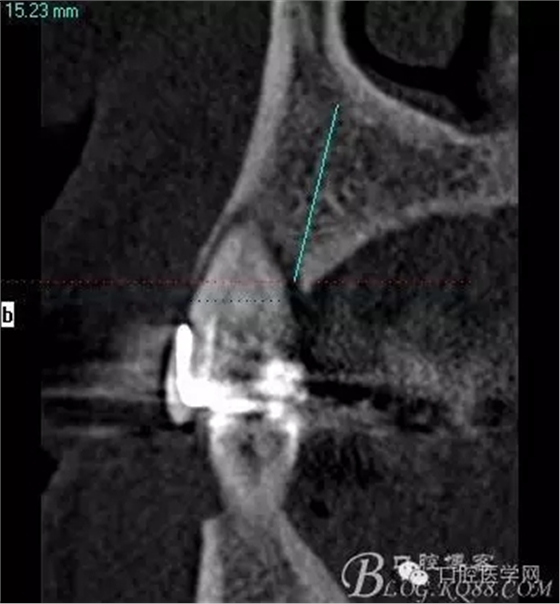

術(shù)后片顯示方向非常可以

頰顎向的方向也很理想 箭頭所示 空間填滿了自體骨